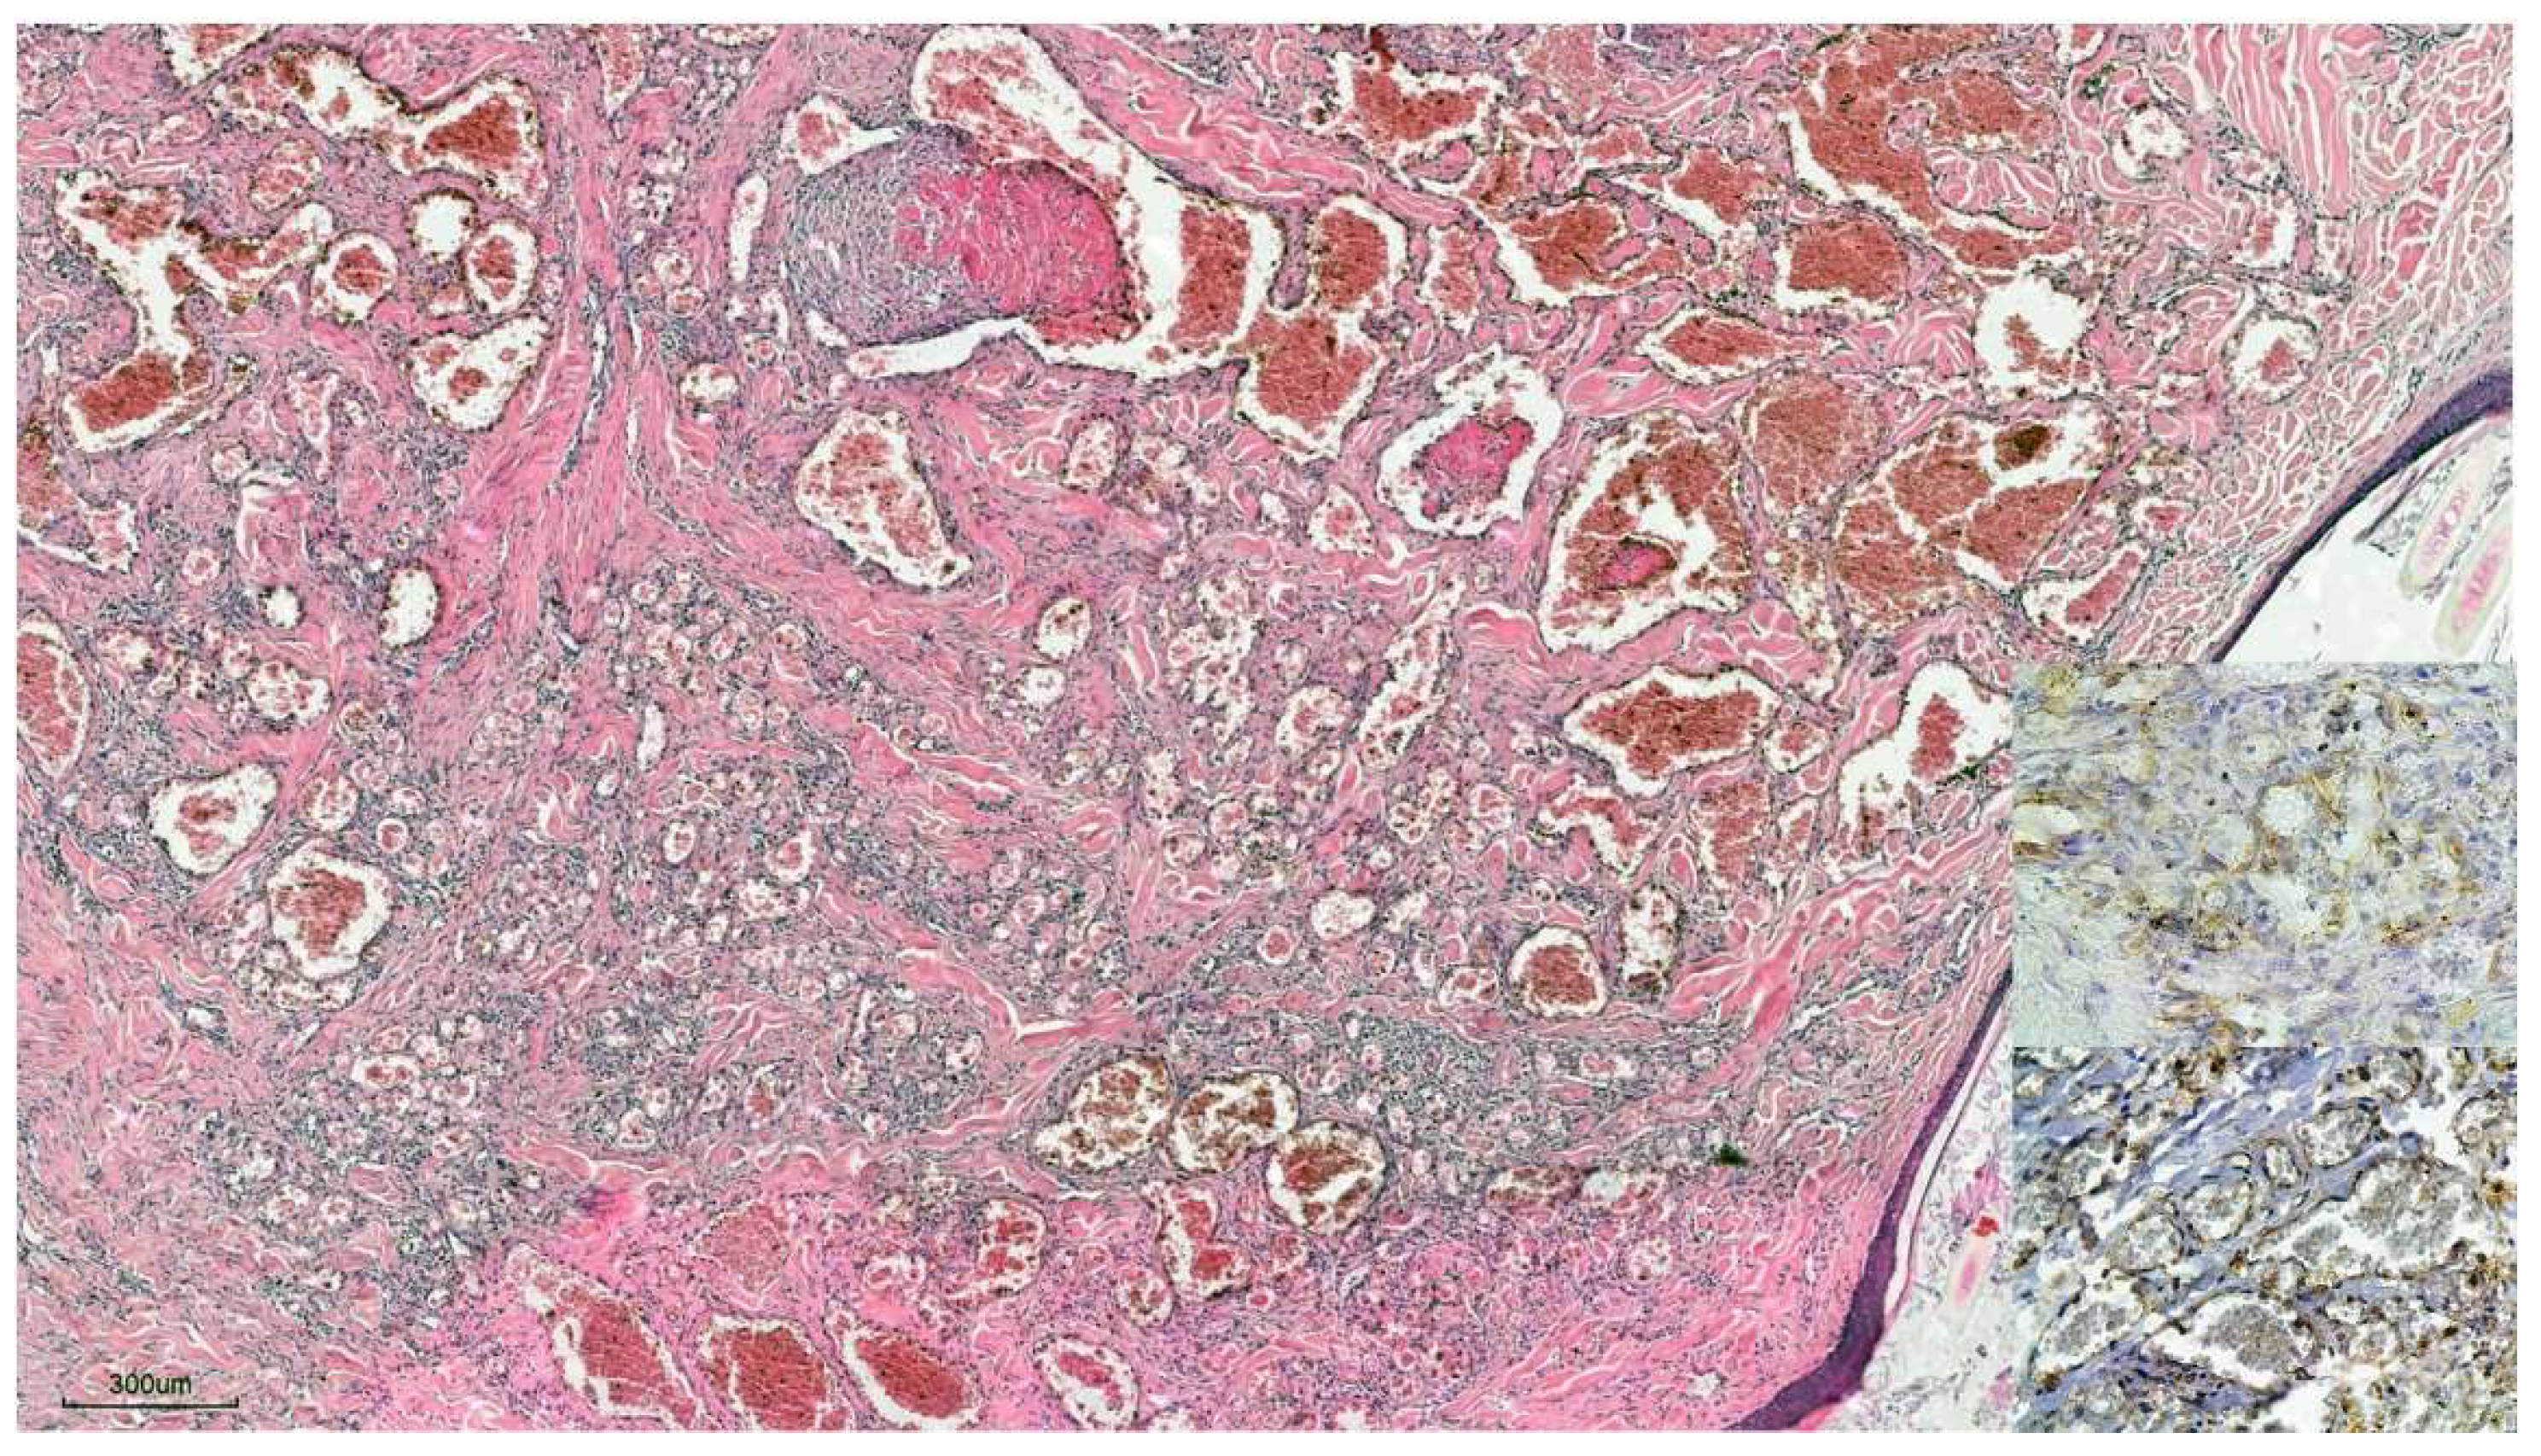

3.1.2. Histopathology

3.1.3. Immunohistochemistry

3.2.2. Histopathology

3.2.3. Immunohistochemistry